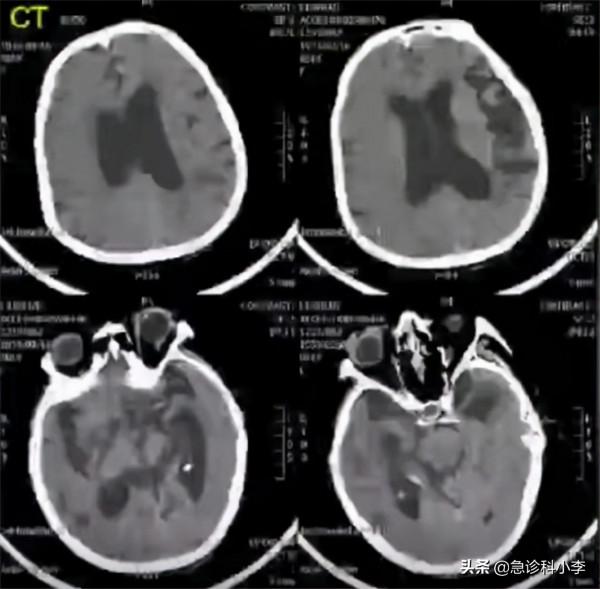

陳先生進入搶救室後,我們給他做了急診CT和MRI,排除了腦出血問題,但是發現了腦內多處梗塞灶,確診為腦梗死。

透過頭顱彩超,我們發現顱內動脈出現狹窄,顱內血流動力嚴重不足,確診為急性腦缺血,我們透過靜脈溶栓治療,疏通腦血管,緩解腦缺血現象和腦梗塞。